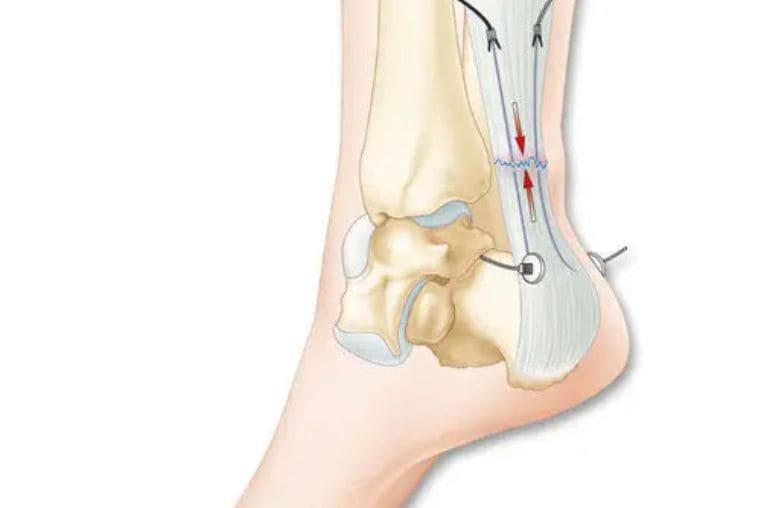

A cirurgia é indicada para casos de deformidades graves, instabilidade crônica ou fraturas complexas que não respondem ao tratamento inicial. Se você sofre com dores no pé ou tornozelo, agende uma avaliação com o Dr. Alessandro Leite para um diagnóstico correto e um plano de cuidado focado em você.